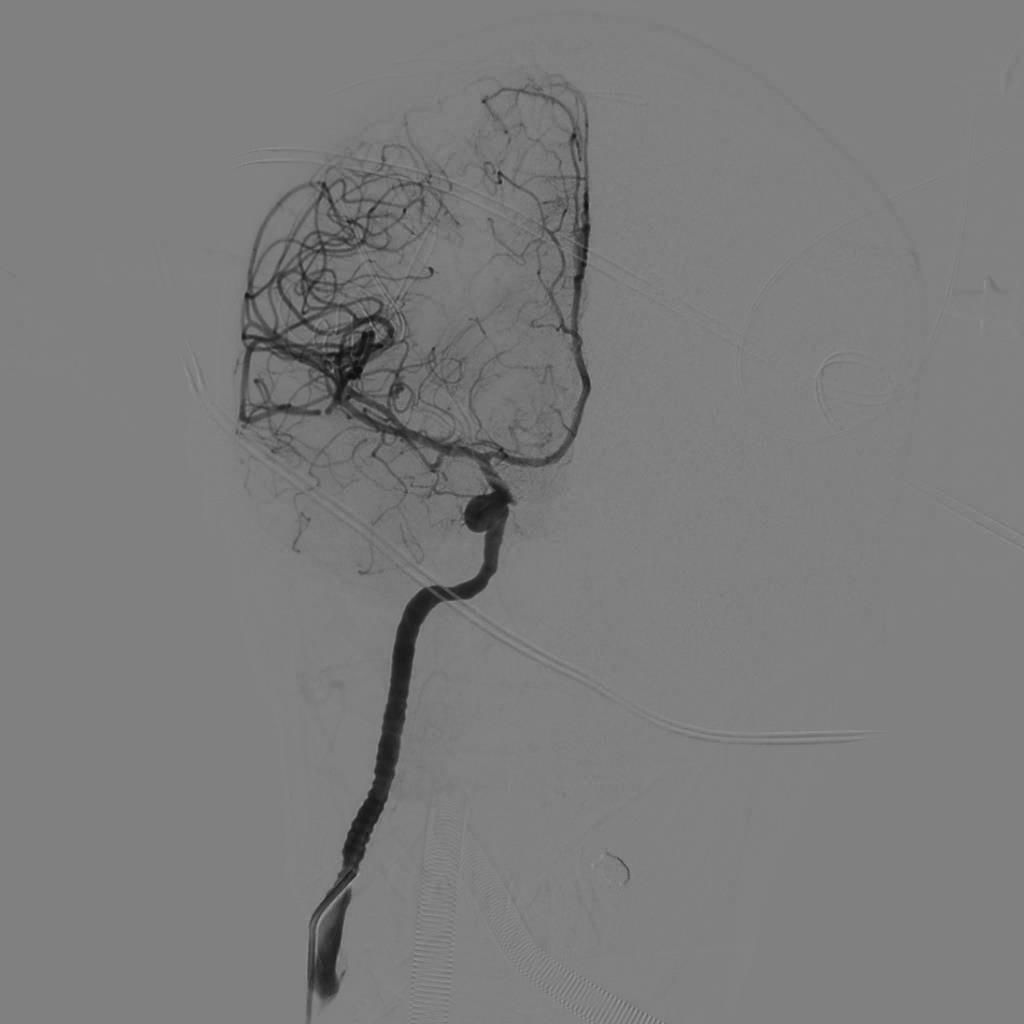

入院后完善DSA检查提示颅内多发动脉瘤:右侧颈内动脉眼段大动脉瘤(约18*19mm,瘤颈6.6mm),左侧眼动脉段及床突段动脉瘤。和家属沟通病情,告知介入和开颅手术风险利弊后,患者家属选择开颅动脉瘤夹闭手术治疗。进一步行DSA+CT融合,模拟手术入路视角。

全身肝素化后,路图下将6FGuiding导引导管放置于右侧颈内动脉岩谷水平段,使用Scepter球囊微导管在014微导丝带领下超选进入颈内动脉岩谷垂直段,充盈球囊,造影显示阻断颈内动脉满意后继续手术。

球囊到位

球囊充盈,虚线为球囊

球囊阻断满意,造影剂返流至颈外动脉,虚线为球囊

再次探查动脉瘤发现瘤体表面张力明显下降,探针分离瘤颈,以2枚直动脉瘤夹792+760夹闭瘤颈。解除球囊阻断后,动脉瘤表面张力无回升,穿刺瘤体无活动性出血。荧光造影提示瘤体无显影,载瘤动脉血流通畅,无明显狭窄,各分支保留完好。切除部分瘤体,视神经减压。DSA复查提示动脉瘤夹闭满意,全脑血管通畅后关颅。(球囊阻断时间约10分钟)